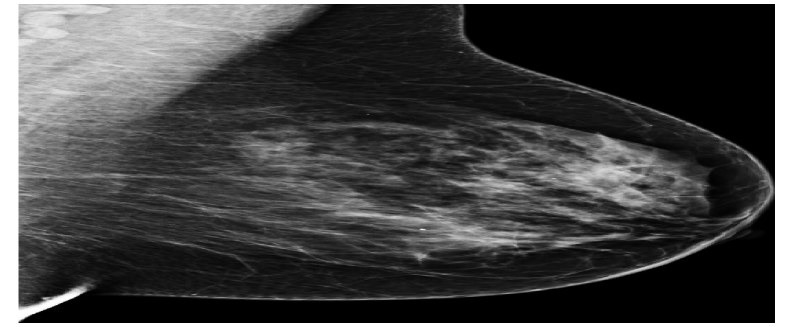

As data augmentation, random Gaussian noise (μ=0\mu=0, σ=0.005\sigma=0.005), random horizontal flipping (p=0.5p=0.5), random rotation (15-15^{\circ}, +15+15^{\circ}), random translation (0, 0.1), random shearing (25-25^{\circ}, +25+25^{\circ}), scaling by a random factor between 0.8 and 1.6 were used. Three standardized mammography images from different datasets are shown in the Figure 6.

Refer to caption

(a) Hacettepe

(b) VinDr

(c) CSAW

Figure 6: Standardized mammography samples from Hacettepe, VinDr, and CSAW dataset.